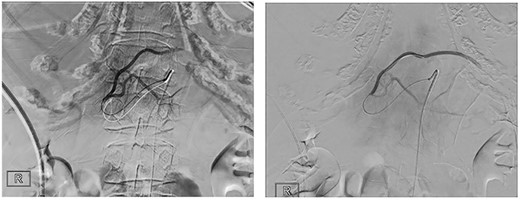

The patient was transferred to the interventional operating room for embolization of the left hepatic artery. Digital subtraction angiography (DSA) showed active contrast agent extravasation (Fig. 2). The tumour was embolized with 500–700 μm beads followed by gel foam. The patient remained hemodynamically stable throughout the procedure.